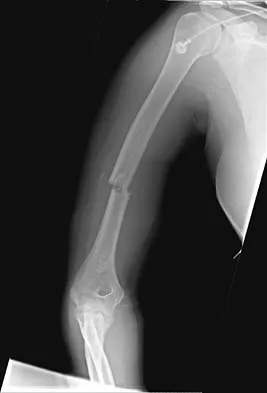

A 20-year-old woman sustained the closed injury shown in Figures 49a and 49b in a motor vehicle accident. Examination reveals that this is an isolated injury; however, she has a complete radial nerve palsy. Management should consist of

Lacerated radial nerves are associated with open humeral fractures. All open humeral fractures with radial nerve palsy should be managed with radial nerve exploration and skeletal stabilization. Closed humeral fractures with associated radial nerve palsy usually have an intact nerve with neurapraxia. Most of these patients recover without surgical treatment. If the patient has multiple injuries, skeletal stabilization may be indicated to improve mobilization. For an isolated closed humeral fracture with a radial nerve palsy, the treatment of choice is splinting for 1 to 2 weeks, followed by a humeral fracture brace. Ring D, Chin K, Jupiter JB: Radial nerve palsy associated with high-energy humeral shaft fractures. J Hand Surg Am 2004;29:144-147.